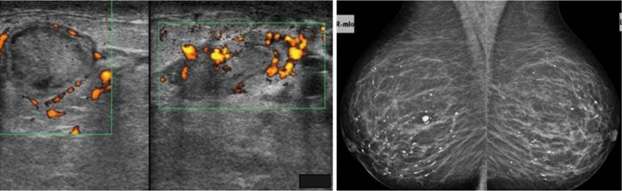

Idiopathic granulomatous mastitis is another uncommon type of non-lactational mastitis that is usually seen a few years after lactation. The etiology and pathophysiology are also unclear but are currently thought to be related to an autoimmune process against specific antigens in extravasated milk. A reaction to breast trauma, subclinical infection (specifically with Corynebacterium species), and hyperprolactinemia have also been implicated in the etiology. It is thought that the resultant destruction of acini and milk ducts causes leakage of milk into breast tissue, triggering a localized inflammatory cellular infiltrate and ultimately a granulomatous response. Granulomatous mastitis usually presents as a unilateral firm breast mass, with or without skin thickening and ulceration, nipple retraction, and adenopathy. Often, patients present with extramammary symptoms including arthralgias and skin changes. Mammographic and sonographic appearance is variable. Mammograms are often normal but can also demonstrate asymmetrically increased density or multiple benign or malignant appearing masses. Ultrasound findings can include a mass-like appearance, tubular or nodular hypoechoic structures, or an ill-defined hypoechoic area. In the workup of this condition, other causes of granulomatous disease should be excluded, including sarcoidosis, granulomatosis with polyangiitis, tuberculosis, and fungal infection. Additionally, given similarity in presentation and imaging appearance, an underlying breast cancer should be excluded, and diagnosis is usually confirmed with biopsy of suspicious lesions. Complications also include abscess and fistula.

Case: Mastitis Figure 3

Figure 3. Images from Oztekin et al. show imaging features associated with a case of biopsy-proven granulomatous mastitis. Mammographic images on the left show asymmetric increased density particularly within the lateral aspect of the right breast. Ultrasound on the right shows a corresponding heterogeneous ill-defined hypoechoic region with tubular extensions.